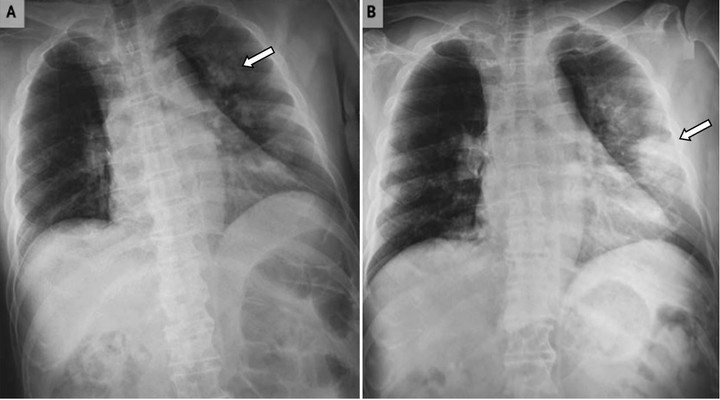

Xơ phổi vô căn ảnh hưởng đến các hoạt động hàng ngày của bệnh nhân như gây khó thở. (Ảnh minh họa)

Xơ phổi vô căn ảnh hưởng đến các hoạt động hàng ngày của bệnh nhân như gây khó thở, các cơn ho khan và dai dẳng, tức ngực và ngón tay dùi trống. Đây là một căn bệnh chưa được biết đến rộng rãi, đặc biệt tại Việt Nam, có khoảng 90% bệnh nhân mắc phải bệnh xơ phổi vô căn không biết đến các triệu chứng của căn bệnh nguy hiểm này, và một số khác lại nhầm lẫn với các triệu chứng của các bệnh phổi và tim thông thường.